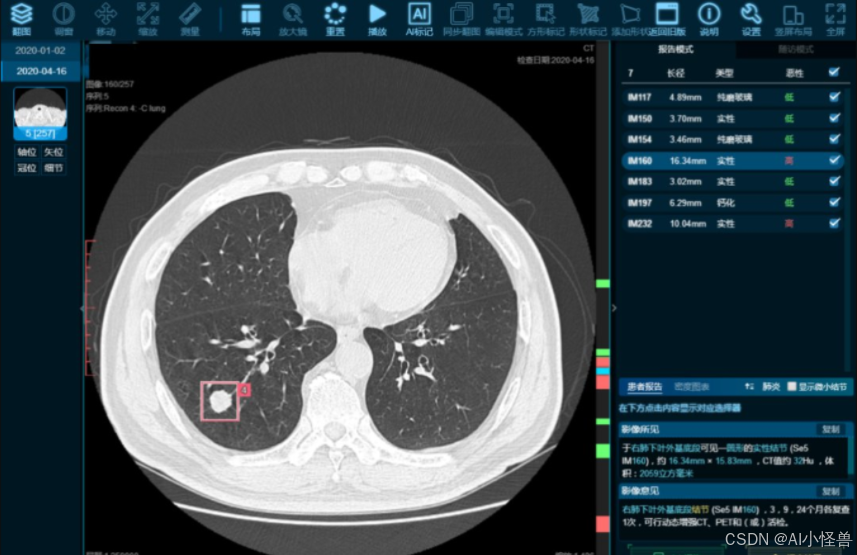

到2025年,YOLO系列算法将继续在实时目标检测领域保持领先地位,其网络架构优化、多模态融合、边缘计算适配等多方面的进步,将使其在工业、自动驾驶、医疗、农业、安防等领域的应用更加广泛和深入。

医疗与健康:YOLO将结合医学影像和患者数据,用于疾病检测和诊断,提升医疗响应的个性化和准确性。